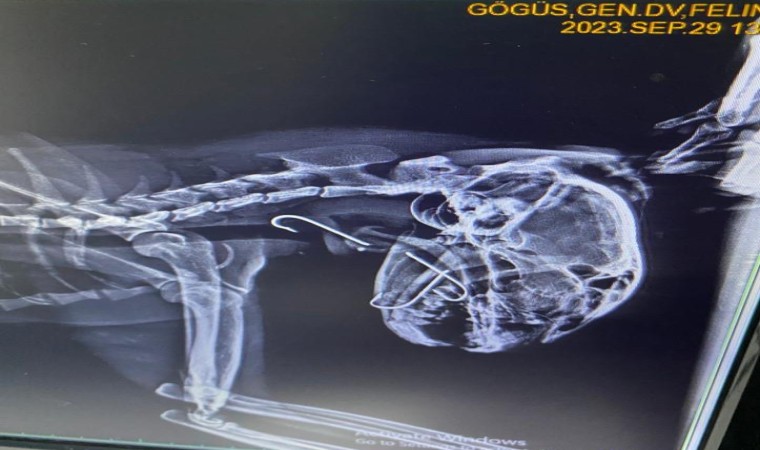

Kilimli ilçesinde bir sokak kedisinin ağzında kanca olduğunu gören vatandaşlar durumu hayvansever Seda Mercan’a iletti. Kediyi bulan Mercan, zabıta ekiplerinden yardım istedi. Veteriner hekime getirilen sokak kedisinin röntgeninde boğazına saplanmış üç tane olta kancası olduğu tespit edildi. Ameliyata alınan kedinin boğazındaki kancalar çıkartıldı. Yaklaşık bir saat süren ameliyatta kancaların derine saplandığı görüldü. Ameliyattan sonra kedi sağlığına kavuşurken veteriner hekim Furkan Alkan, süreci şöyle aktardı:

"Vaka geldiği zaman ağzında salya akıntısı ile geldi. Üç günden beri bu haldeymiş. İlk yaptığımız muayenede kancanın bir kısmını gördük ve hemen röntgeni çektik. Röntgende 3 tane kancanın boğazına takıldığını gördük. Endoskopi yardımıyla 3’ünü birden çıkardık. Üçü de çok derine saplanmıştı. Yarım saat bir saatlik bir operasyonla arkadaş sağlığına kavuştu. Ya balık alırken ya da balıkçılar tarafından atılan balığı kaparken kancayla beraber kaptı. Kancaları yuttu. Oraya saplandığı için de ne ağızda kaldı ne de mideye gitti. 3-4 günden beri enfeksiyonlu ağız akıntısı varmış, kliniğimize gelip tedavisini gördü. 4-5 yaşlarında sokak hayvanı. Bir hayvansever tarafından getirildi. Masraflarını hayvansever karşılıyor."